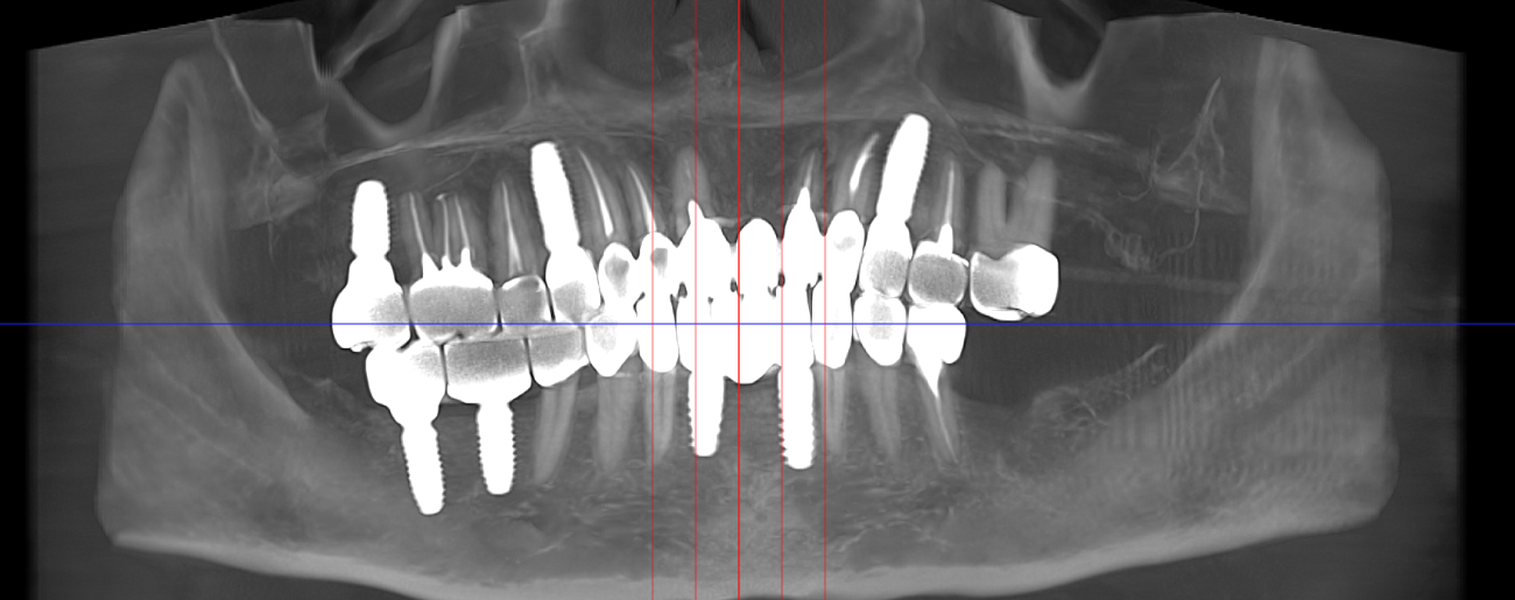

Tomografii (CBCT)

Caz 1

Caz 2

Reabilitarea complexă în stomatologie presupune refacerea completă a sistemului dentoalveolar, atât din punct de vedere funcțional, cât și estetic. Procesul începe cu o examinare detaliată a cavității bucale, interpretarea investigațiilor imagistice (CBCT), evaluarea musculaturii, articulațiilor temporomandibulare și a parametrilor estetici.